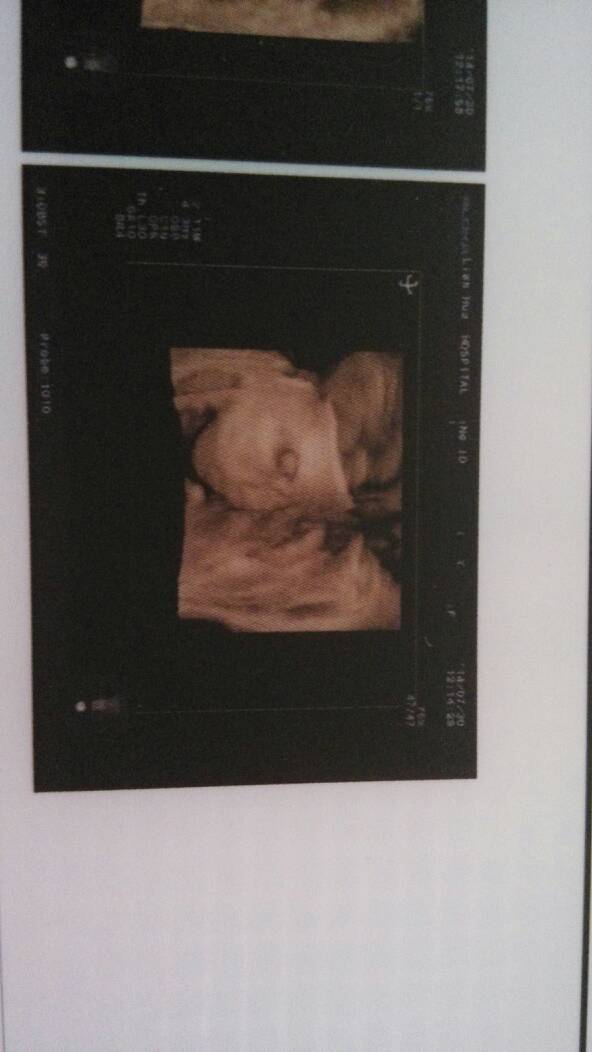

三维彩超跟四维的差别在哪呢?我上周做了三维彩超,我感觉宝宝脸蛋看得挺清楚的,还感觉跟老公特像,大家 三维彩超跟四维的差别在哪呢?我上周做了三维彩超,我感觉宝宝脸蛋看得挺清楚的,还感觉跟老公特像,大家帮我看下,这个明显的宝宝的五官吧,又怕自己看错 点击展开 爽爽~~ 2014-08-06 17:05 为您推荐: 其他回答 清晰了!, 婷,琳麻麻 2014-08-16 21:43 可以,看的清楚 冷暖自知。 2014-08-16 20:17 差别就是三维彩超的照片是静态的。四维彩超的是动态,效果是一样的 婷,琳麻麻 2014-08-16 14:57 还可以看清!!! 豆豆麻麻乀 2014-08-06 17:19 相关问题 请问一下,四维,和三维彩超,有什么不一样?做那个更好? 今天四维了,看到宝宝的手、脚、脸各方面很健康、我和老公好高兴 6个月做了三维彩超 以后还要在四维吗